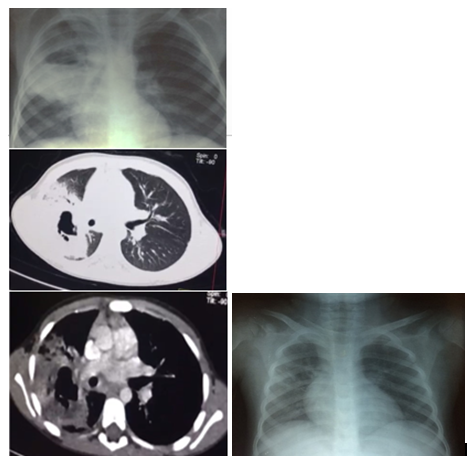

A 5-years-old Egyptian boy who was born to consanguineous parents (first degree cousins). His past history was free apart from cervical lymphadenitis reported at the age of 6 months which has been treated successfully with antibiotics and recurrent dental abscesses starting at the age of 2years. In August 2017, he complained of high grade fever for one week associated with mild cough, he received intramuscular antibiotics for 5 days with no improvement. Then he developed pallor, severe cough and grunting and received his first packed RBCs transfusion and was referred to our institution. At presentation, he was ill-looking with high-grade fever, pallor and cough. His weight was 15kg (5th percentile), his height was 101 cm (5th percentile). His examination showed decreased air entry on the right lung and hepatosplenomegaly. His initial laboratory investigations revealed, normocytic normochromic anemia, leukocytosis with neutrophilia, platelet count and elevated acute phase reactants. His blood and urine cultures were repeatedly sterile, and he had negative brucella serology, Widal and Tuberculin tests. His chest X-ray revealed a well-defined lesion in the right upper lobe and a CT chest confirmed the presence of a lung abscess (Figure 1). Parenteral antibiotics were started (vancomycin and meropenem) leading to a gradual improvement of his general condition and subsidence of fever within 4 days of initiation of antibiotics. He started to regain his appetite and activity and cough decreased markedly. Both the liver and spleen regressed in size and acute phase reactants normalized. After three weeks, while continuing his antibiotic course, he acutely developed a high-grade unremitting fever, grunting, marked pallor, jaundice, and marked re-enlargement of both liver and spleen despite improved chest condition and radiogram. His laboratory parameters deteriorated as well (Table 1), with pancytopenia, markedly elevated liver enzymes and direct hyperbilirubinemia. Ciprofloxacin was empirically added the possibility of overwhelming sepsis, and suspicion of secondary HLH was raised. Further investigations revealed markedly elevated serum ferritin and triglyceride levels with normal serum fibrinogen level. Bone marrow aspirate was normocellular with increased erythropoiesis and no apparent hemophagocytosis or evidence of hypoplasia (Of note that it was done after 2weeks from the start of HLH therapy; Figure 2). Viral studies including serology for HAV, HBV, HCV, HIV, EBV and CMV were negative. As he had been fulfilling 5 criteria for diagnosis of HLH according to the Histiocyte society 2004 protocol,2. dexamethasone 10mg/m2/day was promptly started and it resulted in a dramatic improvement of fever, rapid regression of the size of liver and spleen and gradual improvement of the general condition. After 14days, the dose of dexamethasone was reduced to 5mg/m2/day then gradually discontinued as the patient’s condition has completely improved. Basic immunological tests including immunoglobulins assay, lymphocyte subsets analysis, and DHR were normal making an underlying immune disorder unlikely. At the next follow up visit, although his clinical condition and routine laboratory investigations had completely normalized after discontinuation of steroids and antibiotics, he still had splenomegaly (span 12cm) and a persistent normocytic normochromic anemia with a normal blood film and serum ferritin. Further investigation of his splenomegaly and persistent anemia with hemoglobin electrophoresis showed Hb S of 62.5%, Hb F 35.7% and Hb A2 of 1.8%. The diagnosis of SCD was further confirmed by the detection of the homozygous mutation at codon 6 [A>T] of the Beta globin gene. Both siblings are sickle cell trait.

Figure 1 A Chest X-ray and CT chest at presentation, B follow up chest X-ray during the event of HLH.